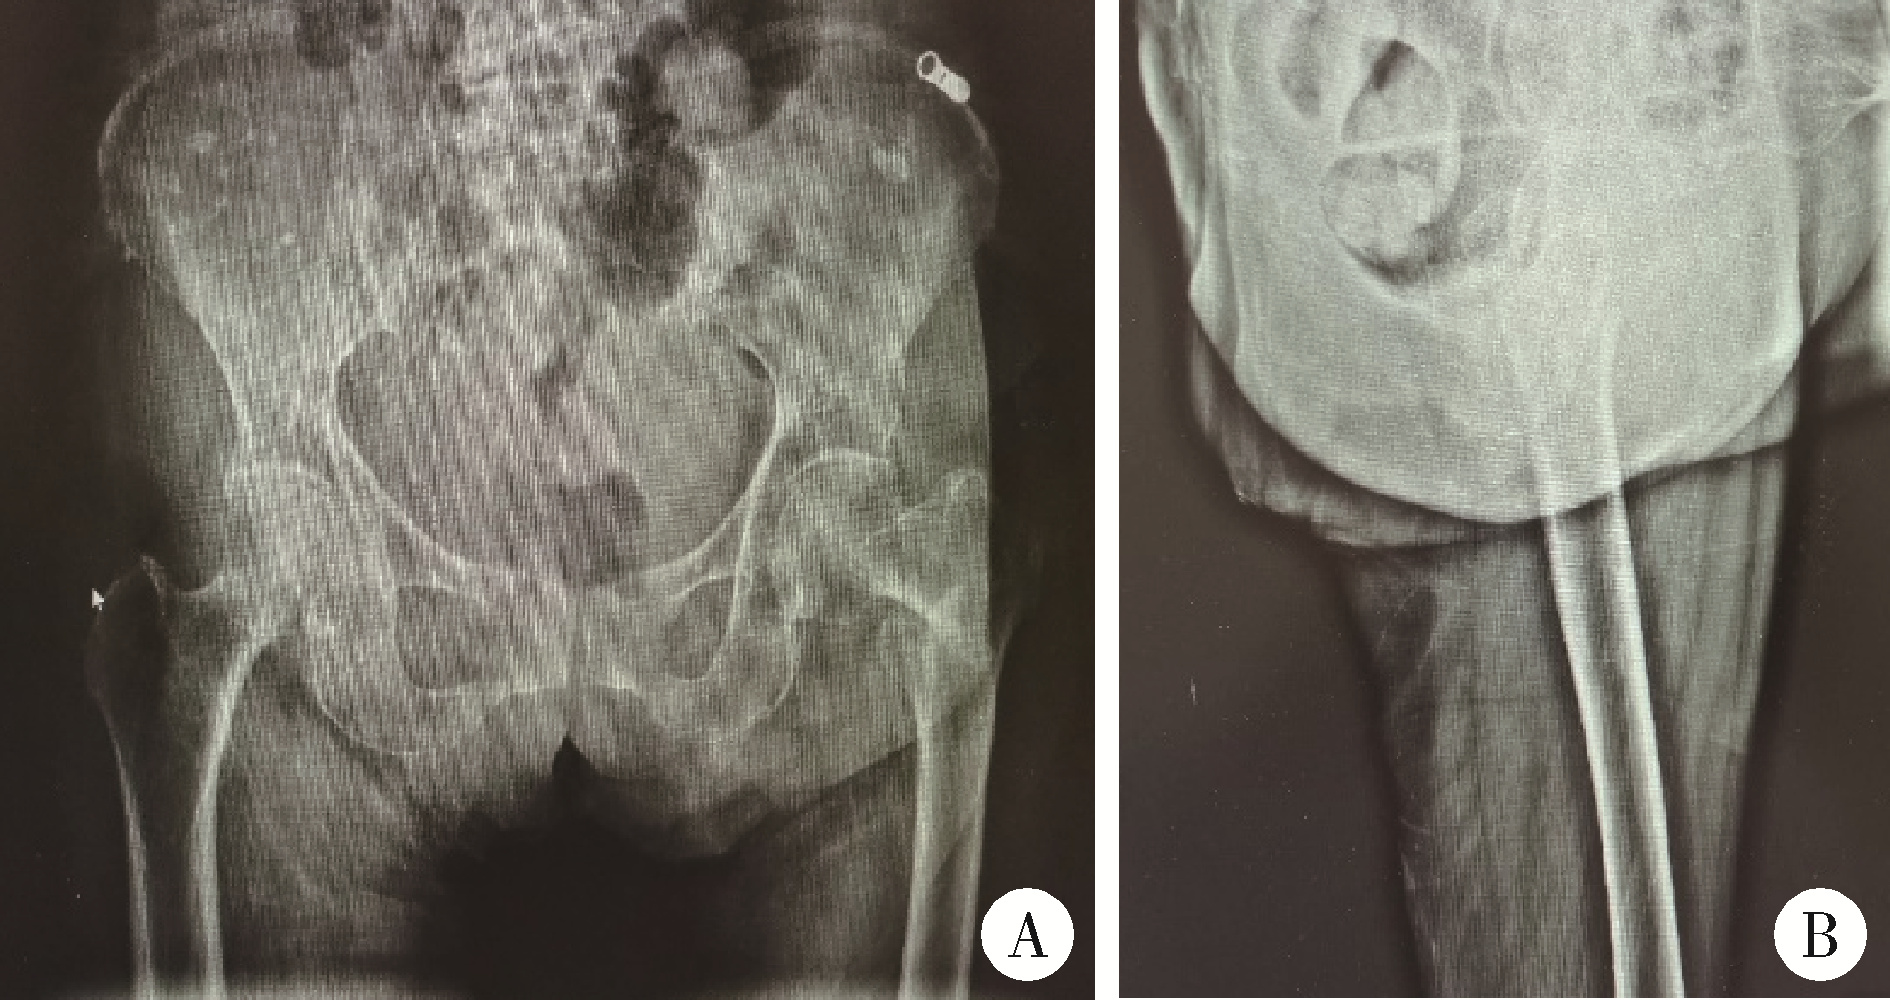

大腿骨近位部骨折って? | 浅井整形外科リハビリセンター|大阪。402_2021_4259_Fig2_HTML.jpg。股骨粗隆间骨折术后同侧股骨颈骨折1例。こちらの商品は裁断機にて裁断済です。ワトソン遺伝子の分子生物学 第7版。確認した限り書き込みやマーカーはありません。裁断済み 麻酔科トラブルシューティングAtoZ。。Dr.森の腹部超音波診断パーフェクト改訂第2版。裁断されてバラバラの状態であることを御理解の上ご購入をお願いいたします。裁断済みのため全体的に状態が悪いとしています。國松の内科学 裁断済み。【裁断済み】臨床に直結する血栓止血学 改訂3版。サージカルテクニック 大腿骨近位部骨折大腿骨近位部骨折の手術手技を詳細に解説した専門書。- タイトル: 大腿骨近位部骨折- サブタイトル: Osteosynthesis & Arthroplasty- 著者: 高橋裕治, 上原秀樹, 神田健二, 北田貴則- ジャンル: 外傷整形外科ご覧いただきありがとうございます。整形外科運動療法ナビゲーション 上下巻セット 上肢 体幹 下肢